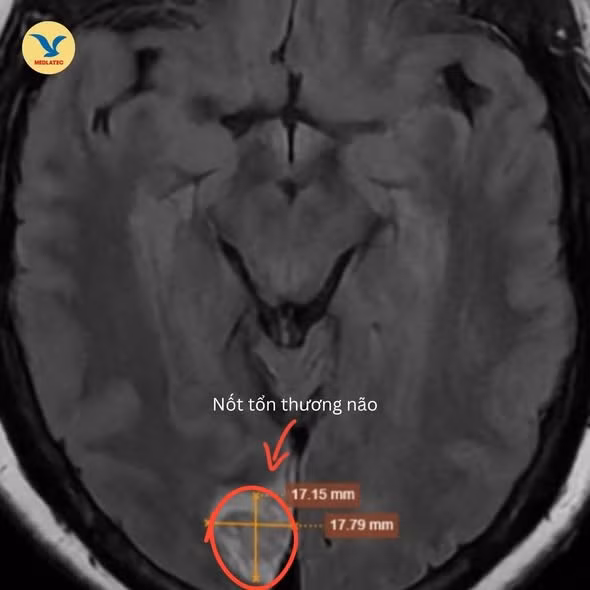

3 tuần sau, bà H. đến Phòng khám Đa khoa Medlatec Tây Hồ để thăm khám. Kết quả xét nghiệm thấy chỉ số mỡ máu tăng cao. Hình ảnh chụp MRI sọ não phát hiện nốt tổn thương vùng chẩm bên phải nghĩ tới tổn thương huyết khối mạn tính hội lưu tĩnh mạch lan vào nhánh nhỏ tĩnh mạch vỏ não lân cận.

Hình ảnh MRI phát hiện tổn thương vùng chẩm - Ảnh BVCC

Bác sĩ chẩn đoán xác định bệnh nhân có nhồi máu vùng chẩm mạn tính do huyết khối hội lưu tĩnh mạch, đây là nguyên nhân gây ra biểu hiện suy giảm thị lực bên phải của bà H.